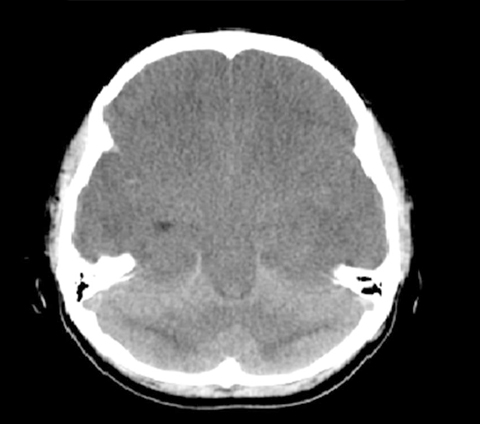

Se tienen convenios de colaboración para la realización de diversos estudios de gabinete con proveedores certificados para: